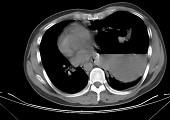

女,6岁,胸闷,咳嗽,胸部CT如图,最可能的诊断为 ( )A.畸胎瘤B.右侧液气胸C.右肺肺大疱D.右侧脓胸E.支气管囊肿并感染